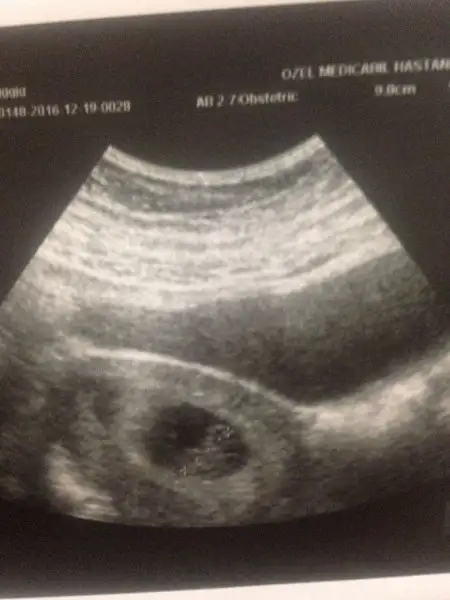

KIZLAR MERHABA 7+3 RESMIMIZ YORUMLAR MISINIZZ

• WhatsApp Image 2016-12-19 at 20.53.57.webp

WhatsApp Image 2016-12-19 at 20.53.57.webp

12,3 KB · Görüntüleme: 112

BIRINDE SOLDA GORNUYOR. ERKEK DIYORLAR SOL OLUNCA AMA BILEMIYORUM TAMDA. KALP ATISI NASIL ?

Canım kalp atışı varmı yokmu bilemedi dr, bebek çok kğçük dedi, atan bişey var ama kalbin atımımı yoksa senin vucudunun atımımı bellş değil dedi, bir hafta sonra tekrar gideceğim